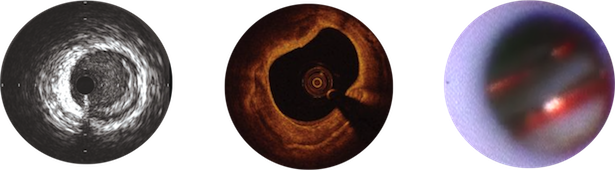

様々な血管内評価機器が使用可能です

血管造影は血管を影絵のように写す検査ですが、血管造影に加えて血管を内側から観察することができる機器に血管内超音波、 OCT、血管内視鏡があります。当院ではいずれの機器も使用可能で、これらの血管内評価機器を積極的に駆使することにより、 より精度の高い検査、治療を実践しています。